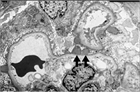

1. 細菌による感染関連糸球体腎炎としては主に溶連菌感染後急性糸球体腎炎、シャント腎炎、感染性心内膜炎による腎炎、IgA優位沈着性感染関連糸球体腎炎がある。